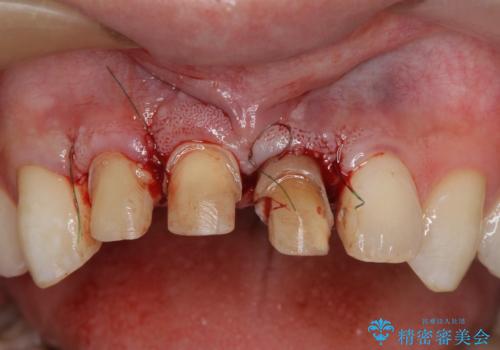

・歯肉縁下カリエス →部分矯正による歯の挺出・歯周外科

歯の挺出を行ったことで歯ぐきの腫れも改善され、安定した歯周環境下でのセラミッククラウン治療を行うことができました。

- 外科手術のため、術後に出血、痛みや腫れ、違和感を伴います